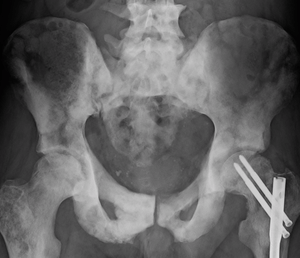

Staging

Diagram showing T1-3 stages of prostate cancer.

An important part of evaluating prostate cancer is determining the stage, or how far the cancer has spread. Knowing the stage helps define prognosis and is useful when selecting therapies. The most common system is the four-stage TNM system (abbreviated from Tumor/Nodes/Metastases). Its components include the size of the tumor, the number of involved lymph nodes, and the presence of any other metastases.[85]

The most important distinction made by any staging system is whether or not the cancer is still confined to the prostate. In the TNM system, clinical T1 and T2 cancers are found only in the prostate, while T3 and T4 cancers have spread elsewhere. Several tests can be used to look for evidence of spread. Medical specialty professional organizations recommend against the use of PET scans, CT scans, or bone scans when a physician stages early prostate cancer with low risk for metastasis.[86] Those tests would be appropriate in such cases as when a CT scan evaluates spread within the pelvis, a bone scan look for spread to the bones, and endorectal coil magnetic resonance imaging to closely evaluate the prostatic capsule and the seminal vesicles. Bone scans should reveal osteoblastic appearance due to increased bone density in the areas of bone metastasis—opposite to what is found in many other cancers that metastasize.